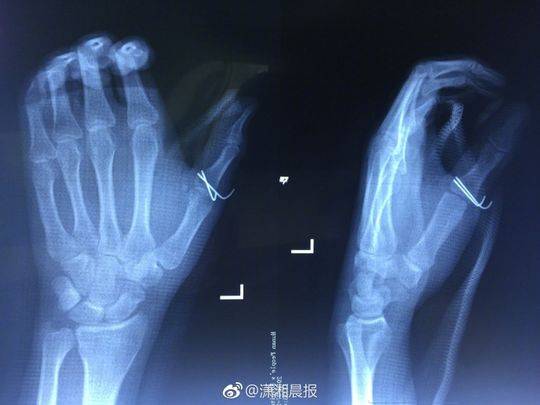

剧烈的疼痛让小袁发出惨叫,家人闻讯赶来一看,只见他的伤口血流不止,受伤的左手也动弹不得,随即将他送往湖南省人民医院急诊一科就诊,医生为其伤口进行了紧急处理。X光检查发现,小袁的左手拇指近节指骨骨折,需进行手术固定,于是将他收入创伤骨病科病房。

当晚10点,该院创伤骨病科何畔副主任医师等为小袁施行" 左手清创探查、左拇指近节指骨骨折切开复位+ 克氏针内固定术",手术历时2小时顺利完成。术后,小袁的左手需采用石膏固定4~6周。